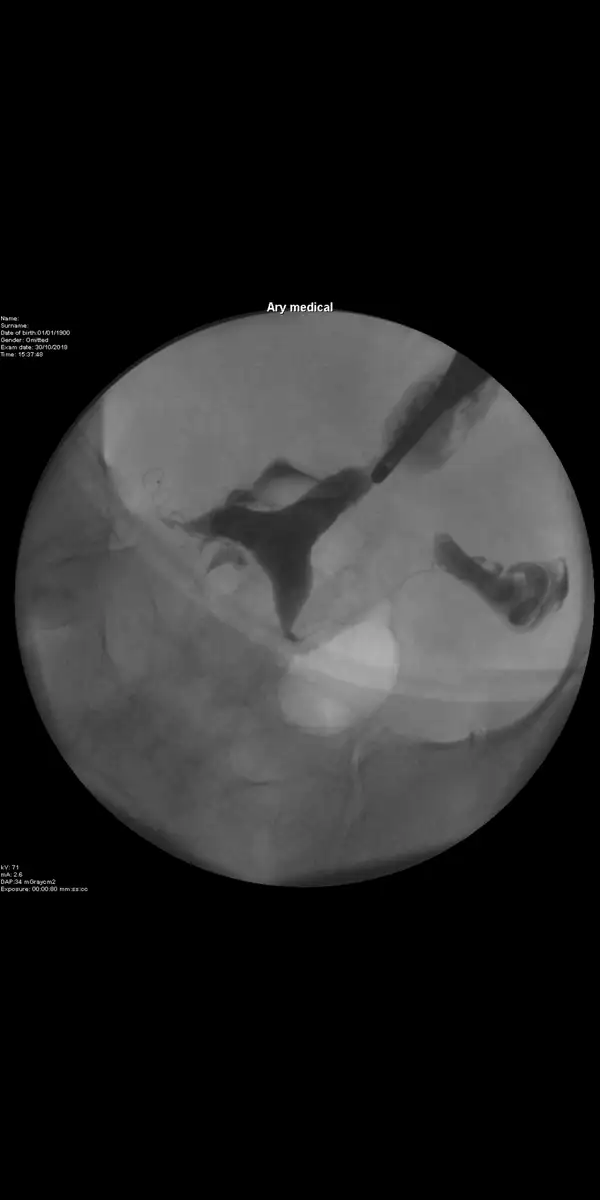

kızlar merhaba aranızda rahim filminden anlayan varmı?filmim nasil çıkmış?doktor bi sorun yok dedi ama pekde aciklama yapmadi.ve cihaz bozuk oldugu icin ameliyathanede cekdi filmi ordaki makineyle

Eklentiler

• Screenshot_2018-12-12-21-41-07-288_com.google.android.gm.webp

7,8 KB · Görüntüleme: 81